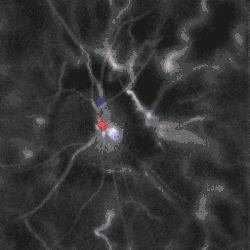

Blood flow in the retina and choroid in the optic disc region can be revealed non invasively by near-infrared laser Doppler imaging.[4] Laser Doppler imaging can enable mapping of the local arterial resistivity index, and the possibility to perform unambiguous identification of retinal arteries and veins on the basis of their systole-diastole variations, and reveal ocular hemodynamics in human eyes.[5] Furthermore, the Doppler spectrum asymmetry reveals the local direction of blood flow with respect to the optical axis. This directional information is overlaid on standard grayscale blood flow images to depict flow in the central artery and vein.[6]

Blood flow in the optic disc revealed by holographic laser Doppler imaging.[4] -

Local direction of blood flow with respect to the optical axis revealed by the Doppler spectrum asymmetry in out-of-plane retinal vessels by holographic laser Doppler imaging.[6] -